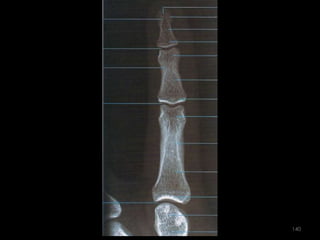

Incidência lateral (lateral-medial ou médio-lateral) dos dedos141

142